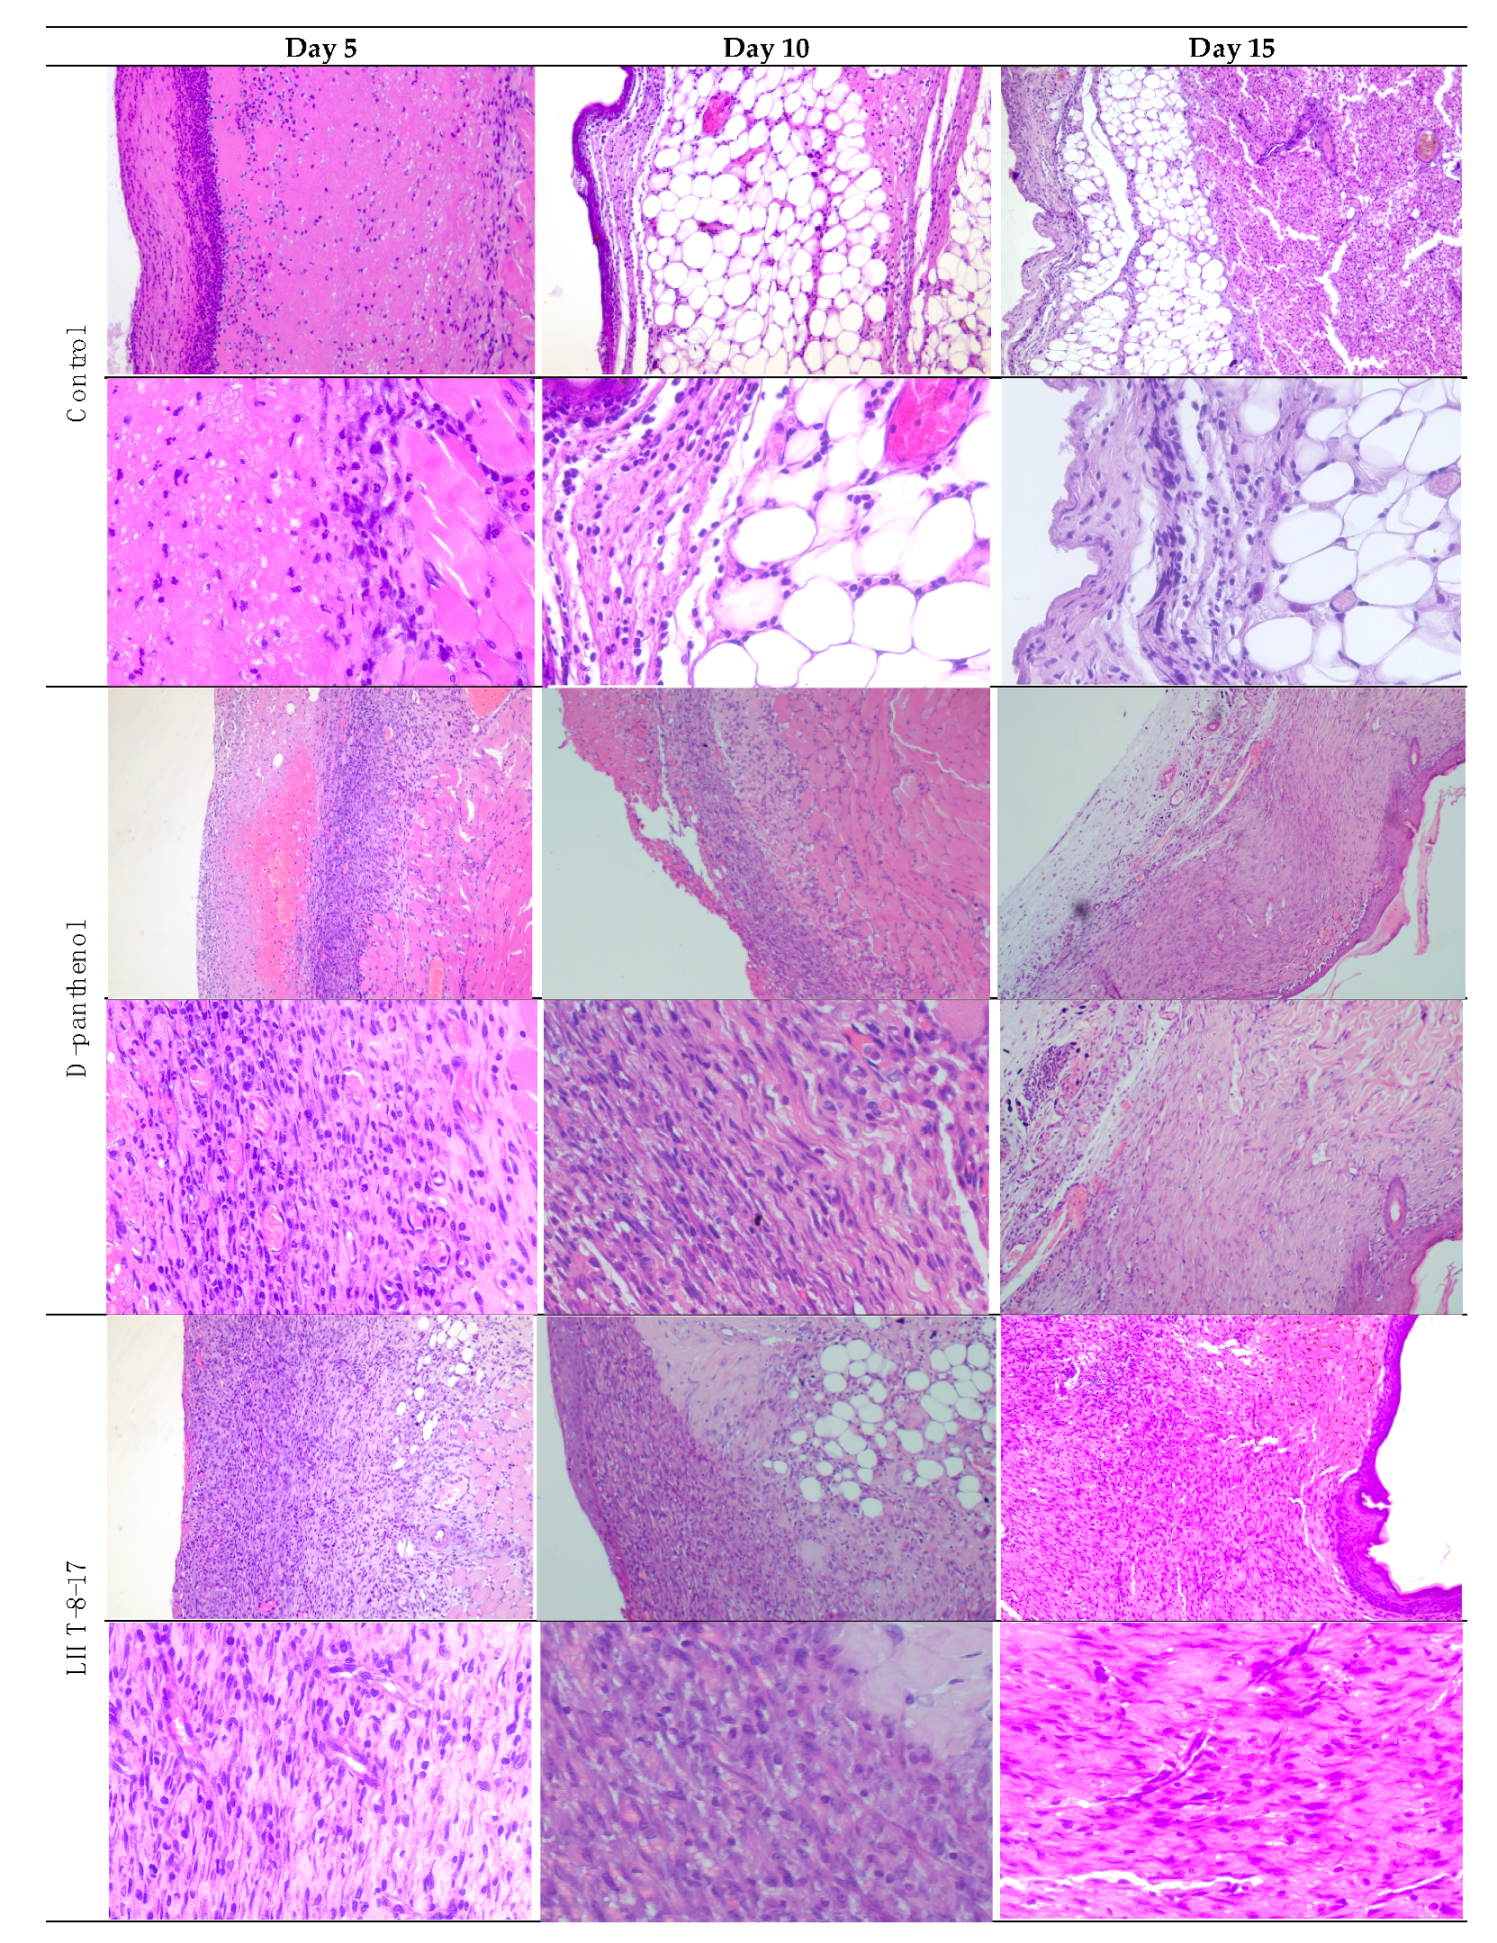

| Day of the Observation | Study Group | Exudation | Presence of Bacterial Colonies | Inflammatory Infiltration | Microcirculation Disorder | Proliferation of Fibroblasts | Neo-Angiogenesis | Prevalence of Granulation Tissue | Maturity of the Granulation Tissue | Fibrous Tissue |

| 5 | D-panthenol | 2 | 0 | 3 | 2 | 1 | 3 | 2 | 2 | 0 |

| LHT-8-17 | 1 | 0 | 2 | 1 | 1 | 3 | 3 | 3 | 0 | |

| Control | 3 | 0 | 3 | 3 | 0 | 0 | 0 | 0 | 0 | |

| 10 | D-panthenol | 0 | 1 | 0 | 3 | 3 | 3 | 3 | 3 | |

| LHT-8-17 | 0 | 1 | 0 | 3 | 3 | 3 | 3 | 3 | ||

| Control | 2 | 0 | 3 | 3 | 2 | 1 | 2 | 1 | 1 | |

| 15 | D-panthenol | 0 | 0 | 0 | 1 | 0 | 3 | 3 | 4 | 3 |

| LHT-8-17 | 0 | 0 | 0 | 1 | 0 | 3 | 3 | 4 | 3 | |

| Control | 1 | 0 | 0 | 1 | 0 | 1 | 1 | 1 | 1 |